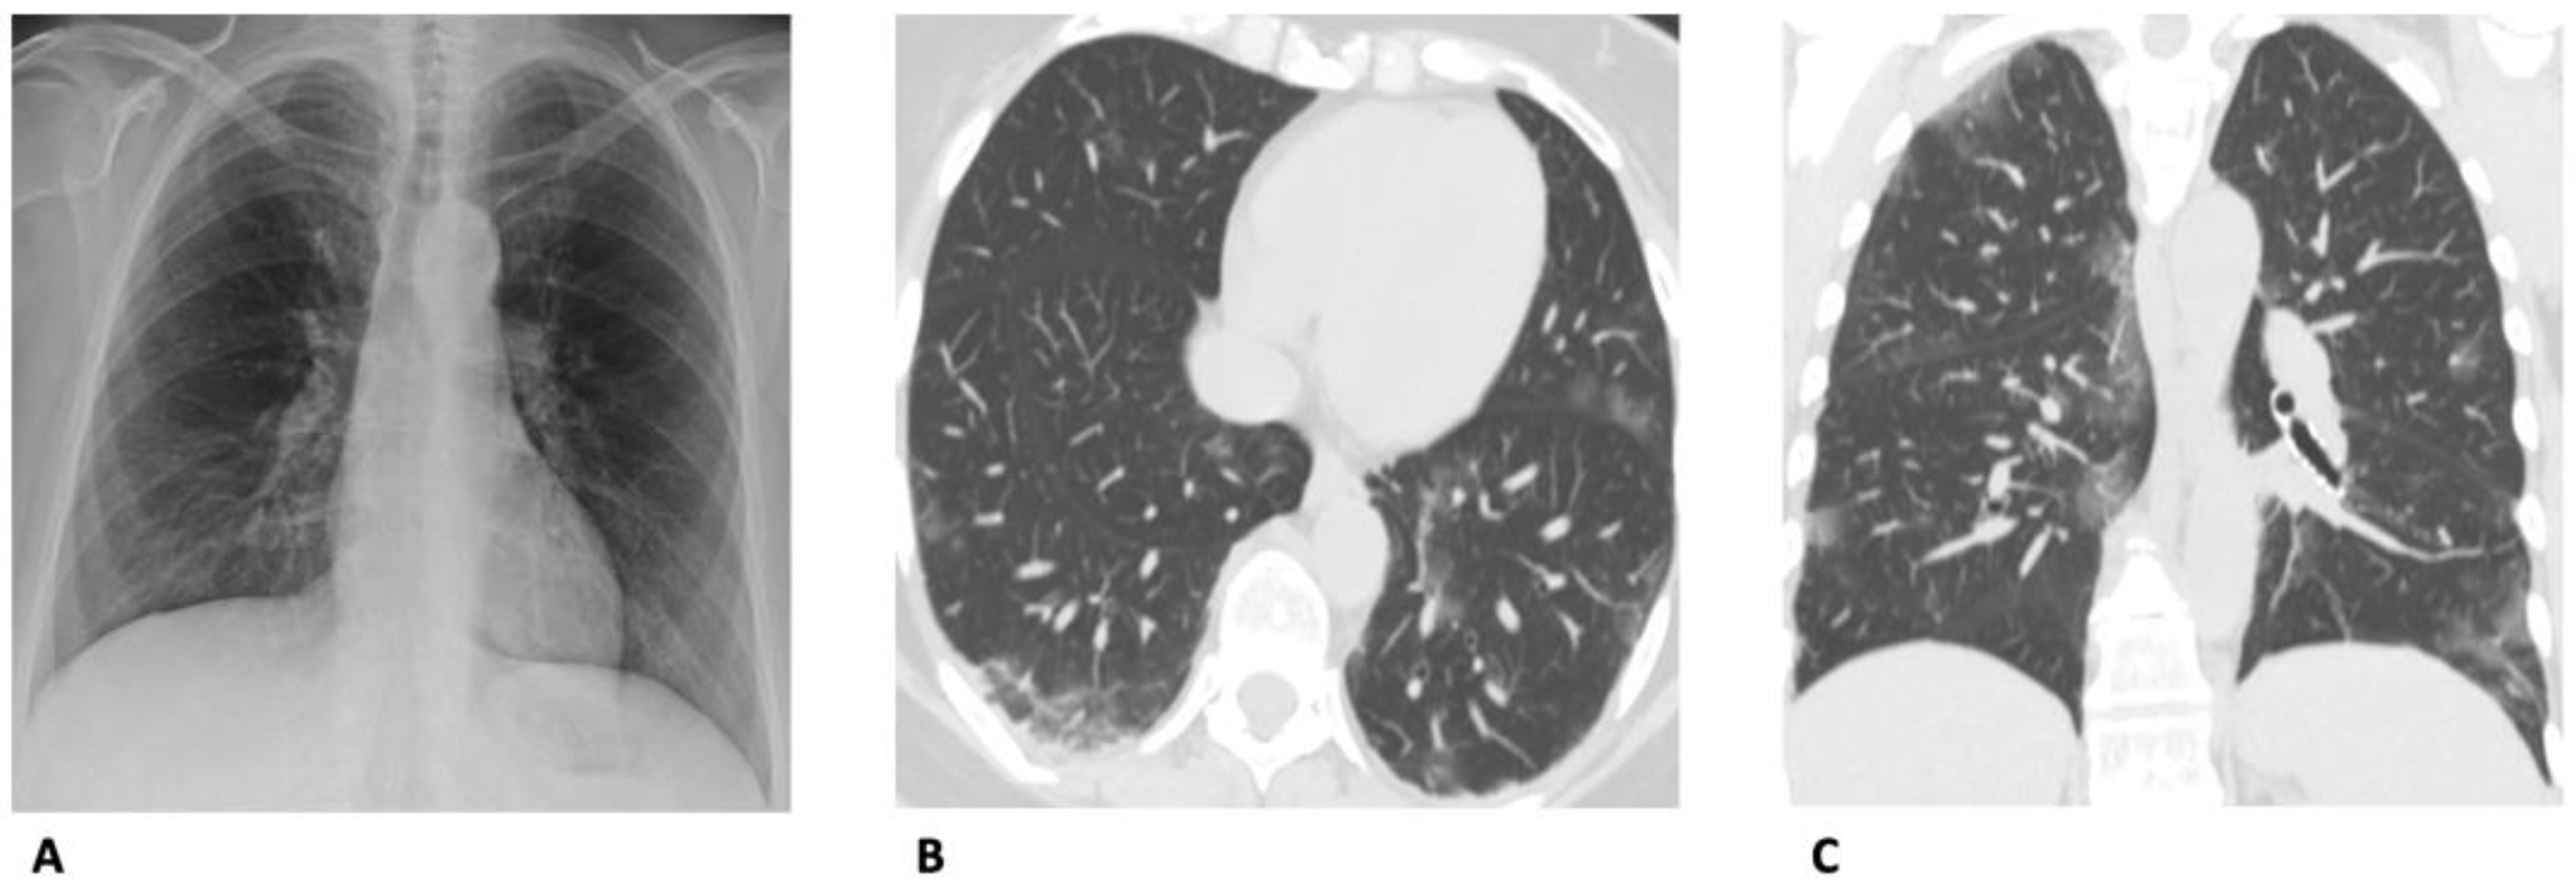

3. Chest X-ray (CXR)

4. Computed Tomography (CT)